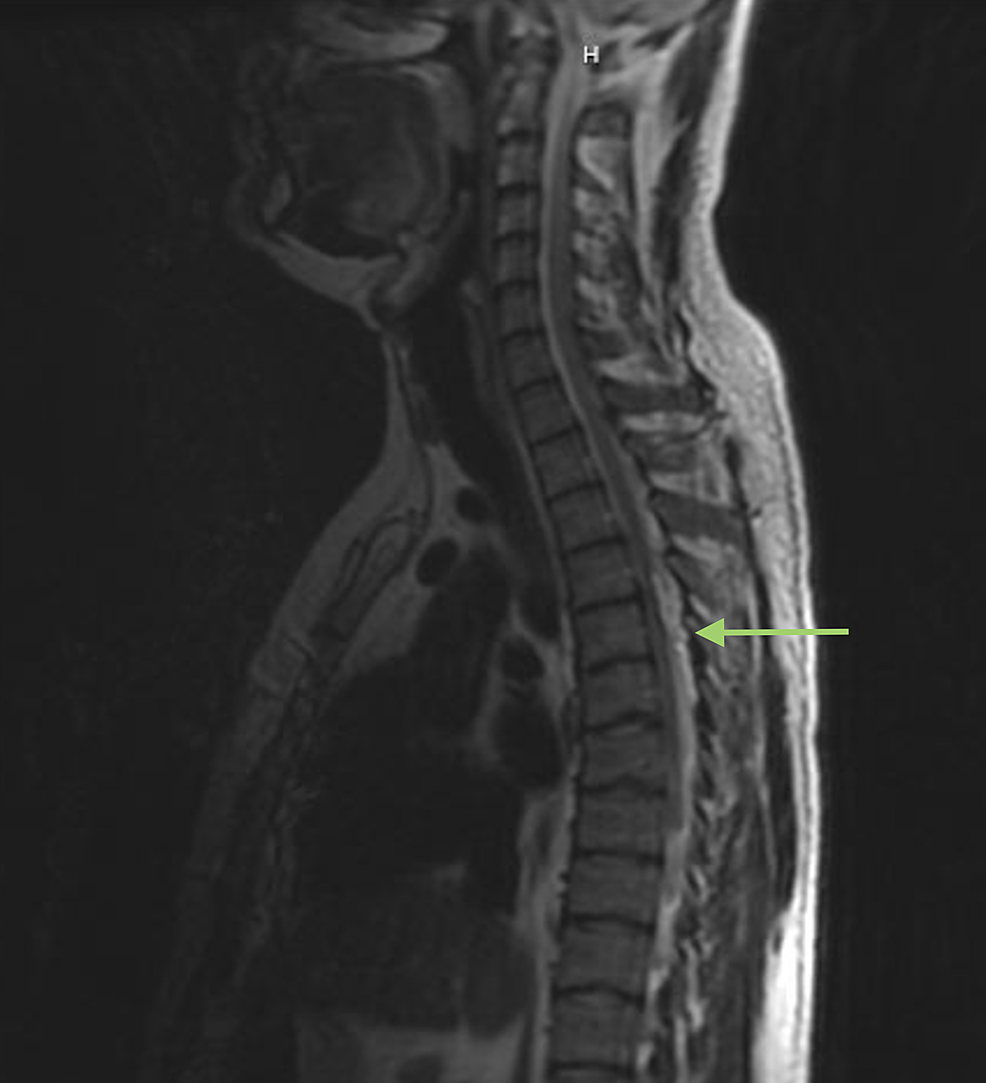

The foremost objective of peer review is the promotion of the highest quality of patient care Peer review is one of the most respected activities in quality assurance and total quality management RadNet’s peer review program helps ensure that our radiologists are competent and practice within the boundaries of professionally accepted norms. The Gulf of Mexico Research Initiative (GoMRI) will select awards for funding by merit review based on peer evaluation, modeled after the National Science Foundation’s Peer Evaluation Process An administrative review of the preliminary and full proposals will take place to ensure that each proposal follows the proposal submission. Radiographers manipulate many parameters during MRI examinations, and image quality can be degraded if sequences are not optimised This may lead to misinterpretation Initial results suggest peer review can result in improved image quality, better protocols, and improved staff confidence There are opportunity costs involved in releasing staff from clinical work and time and resources required for image appraisal training, however we suggest this model can be extended to other departments.